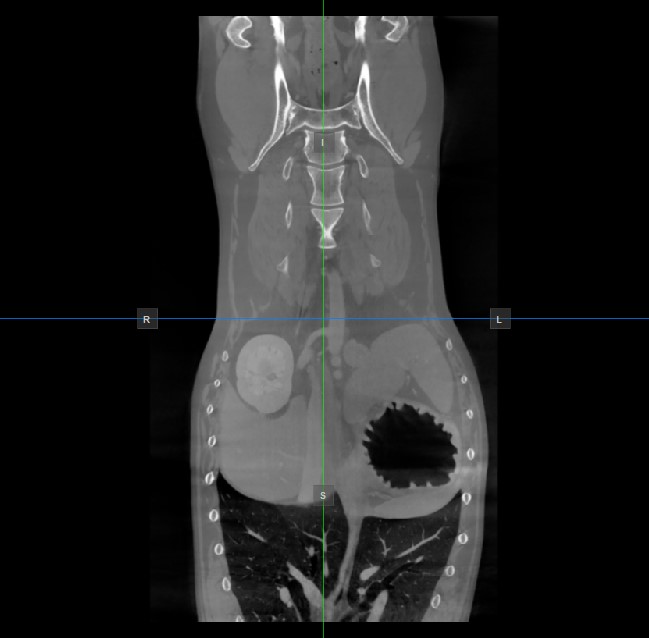

The position and intersection of the other two image planes not represented in the active viewport is indicated by two vertical and horizontal lines called slicers. The endpoints of each slicer are labeled with a letter that corresponds to the appropriate direction/side of the 3D volume, based on the RAS coordinate system.

Only four sides of the available six are indicated on each 2D viewport. The labels and the corresponding side are the following:

Patient Right (R), indicating the right side of the body

Patient Left (L), indicating the left side of the body

Anterior (A), indicating the front side of the body

Posterior (P), indicating the back side of the body

Superior (S), indicating the top side of the body

Inferior (I), indicating the bottom side of the body